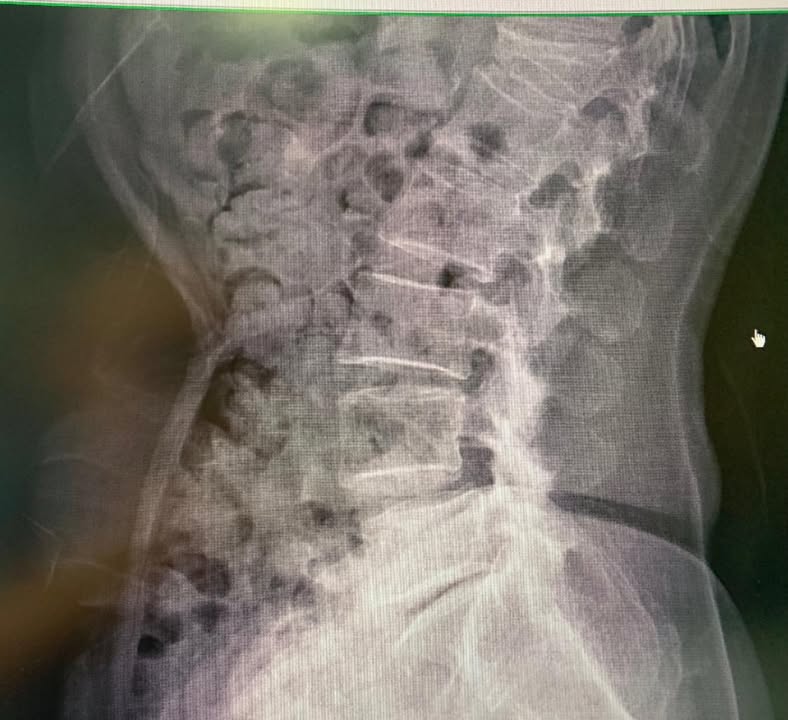

七十歲的李阿姨說雲林北港的蒜農,再來診之前已經大痛快三個月,腳非常的麻痛,上下樓梯也非常痛,走路最嚴重的時候沒有辦法走超過10分鐘,先去當地的復健科診所拍攝片子,就發現腰椎有滑脫的現象,做了一陣子的復健效果仍然不如預期,才去當地的大醫院拍攝核磁共振,更發現椎管狹窄,壓迫雙側神經跟根,因為復健的效果不理想所以神經外科醫生建議開刀治療,女兒介紹特別從雲林北上就醫

診斷:L4 on L5第一度滑脫

L5S1椎間孔第二度狹窄